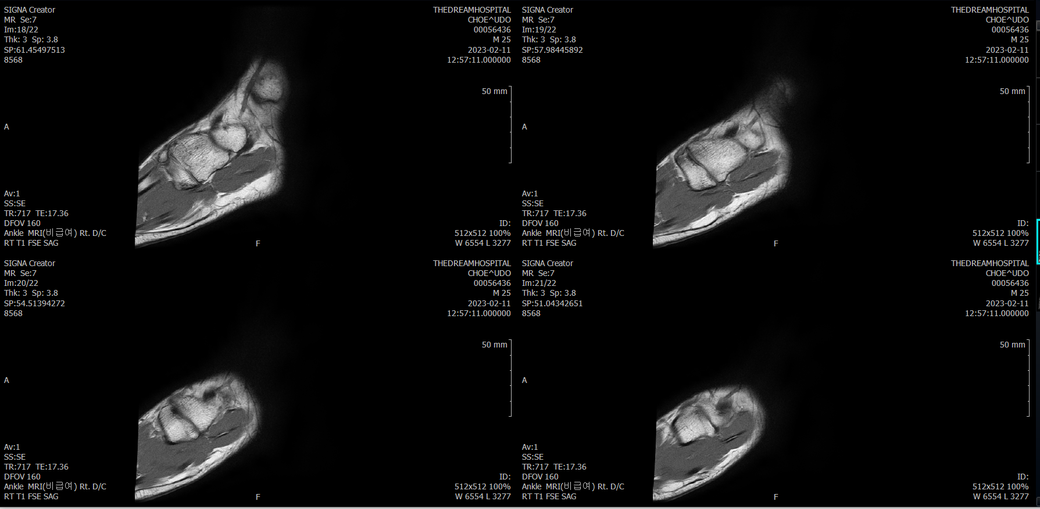

우선 전반적으로 봤을 때 큰 이상은 없어보입니다.

전거비인대 등도 저명한 손상은 없는 것 같아 보이지만, 어느 부분의 통증 등으로 인해 촬영을 하셨는지 말씀을 해주신다면 보다 정확한 병변파악이 가능하겠으며, 병원에서 판독이 완료되신다면 전화 등으로 문의를 해보시는 것이 좋겠습니다.